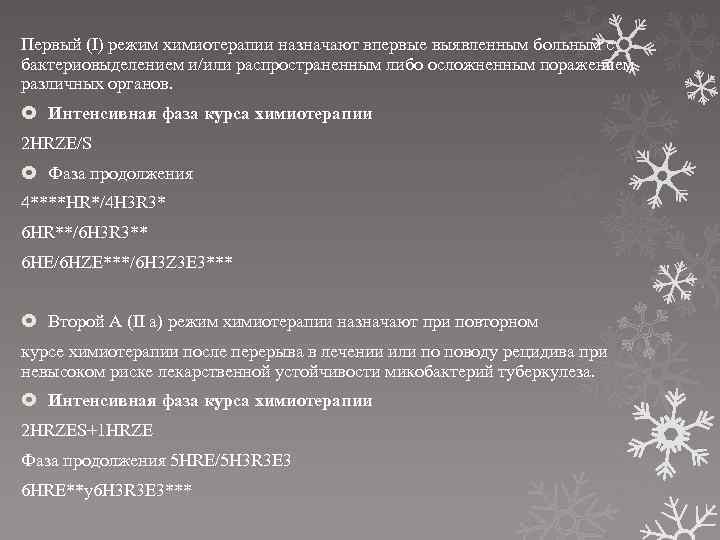

Лечение туберкулеза: Методики химиотерапии

Раздел: Визуальный дайджест